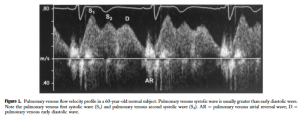

次に示すのが正常のPV flow wave。収縮期波はS1, S2波に分かれており、拡張期波はD波、心房収縮期に心房収縮による逆流波(AR波)が観察されます。S波とD波は正常では順行波です。

([2]より引用: 正常肺静脈波形)

([2]より引用: 正常肺静脈波形)